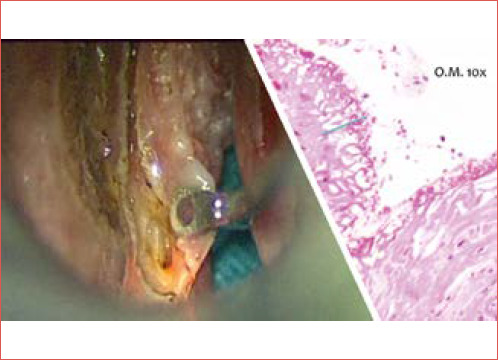

Objective: To evaluate the prognostic significance of surgical margins in patients undergoing transoral laser microsurgery (TLM) for laryngeal squamous cell carcinoma (LSCC).

Methods: A comprehensive literature search was conducted in PubMed/MEDLINE, Cochrane Library, Scopus, and Google Scholar following PRISMA guidelines. Studies comparing oncologic outcomes between positive and negative resection margins were included. Hazard ratios (HRs) for local control (LC), disease-free survival (DFS), and overall survival (OS) were extracted and pooled using a random-effects model to account for inter-study variability.

Results: A total of 26 studies, including 5,463 patients, met inclusion criteria. The pooled log-HR for DFS was 0.93 (p < 0.05), indicating a significantly higher risk of recurrence in patients with positive margins. However, no significant differences were observed for LC (log-HR = -0.76, p = 0.59) or OS (log-HR = 0.16, p = 0.40).

Conclusions: While positive surgical margins significantly impact DFS, their effect on LC and OS remains uncertain. Further prospective studies are necessary to refine treatment guidelines and optimise oncologic outcomes.